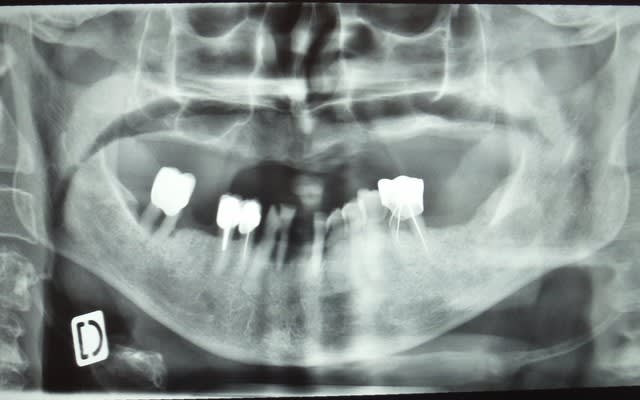

ha ben tiens voila les photo de l'epoque ou je l'ai connu . entre temps il s'est barré voir un aute cd un peu implanto mais pas trop qui lui a viré tout le haut ...

Plus de crête maxillaire et des cônes d'argents vintages, je vais me régaler. Mais en janvier, parce que là... pré-vacances... aucun intérêt à travailler.